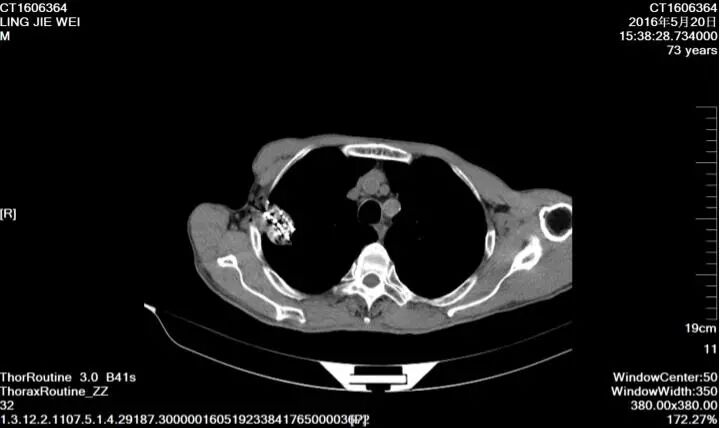

70歲女性,左肺鱗癌,失去手術(shù)及放療機(jī)會(huì),拒絕全身化療,多次行左肺支氣管動(dòng)脈灌注化療;帶瘤生存3年。

73歲肺鱗癌患者,拒絕手術(shù)和放化療,最后選擇放射性粒子植入術(shù),帶瘤生存5年。